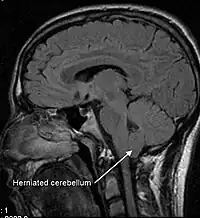

Malformația Arnold-Chiari, sau uneori spus și malformația Chiari este o malformație a creierului. Acestă malformație constă din deplasarea în jos (practic hernierea) a amigdalelor cerebeloase prin foramen magnum (orificiul de la baza craniului), provocând uneori hidrocefalie ca urmare a obstrucției circulației lichidului cefalorahidian (LCR). Malformația Arnold-Chiari poate provoca dureri de cap, oboseală, slăbiciune musculară în cap si față, dificultate la înghițire, amețeli, greață, tulburări de coordonare, în cazuri severe paralizie.[1]

Patologul austriac la sfârșitul sec. al 19-lea a descris așa-numitele malformații Chiari I, II și III. Mai târziu alți cercetători au adăugat la clasificare malformația Chiari IV. Clasamentul descrie gravitatea afecțiunii, cea mai gravă formă fiind IV, tipurile III și IV sunt foarte rare.

- Tipul I – este cel mai frecvent, de obicei asimptomatic în copilărie, dar poate fi însoțit de dureri de cap și simptome cerebeloase

- Tipul II – este însoțit de mielomeningocel lombar și determină apariția paraliziei parțiale sau totale sub defectul spinal. Față de tipul I această formă se acompaniază de dizlocarea vermisului cerebelos și a trunchiului cerebral (acestea vor hernia și ele prin foramen magnum)